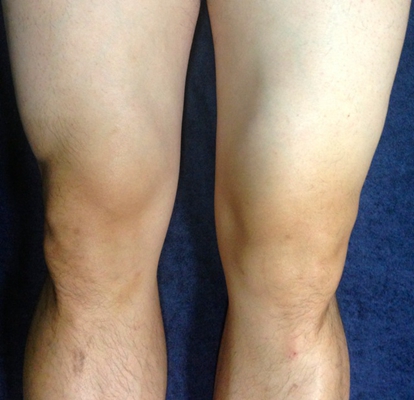

骨質增生圖片

膝蓋骨質增生 (6)